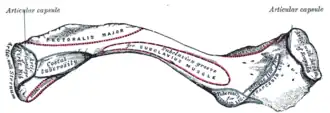

Insertion costale du muscle subclavier (subclavian groove) Insertion claviculaire du muscle subclavier (subclavus)

Insertion claviculaire du muscle subclavier (subclavus) Le muscle subclavier droit